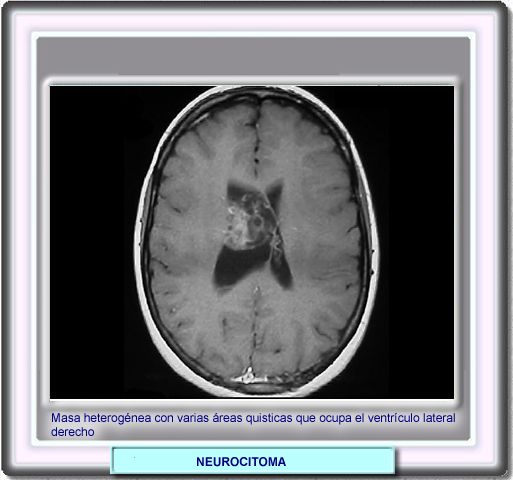

Radiológicamente, los tumores se identifican como masas intraventriculares, a veces de gran tamaño. Las tomografías permiten identificar las calcificaciones, mientras que las RMs muestran masas isointensas con la corteza o con una señal elevada en las imágenes en T1 y T2.

La administración de un medio de contraste suele provocar un resalte homogéneo, si bien si existen áreas quísticas o calcificadas, el resalte puede ser más heterogéneo.